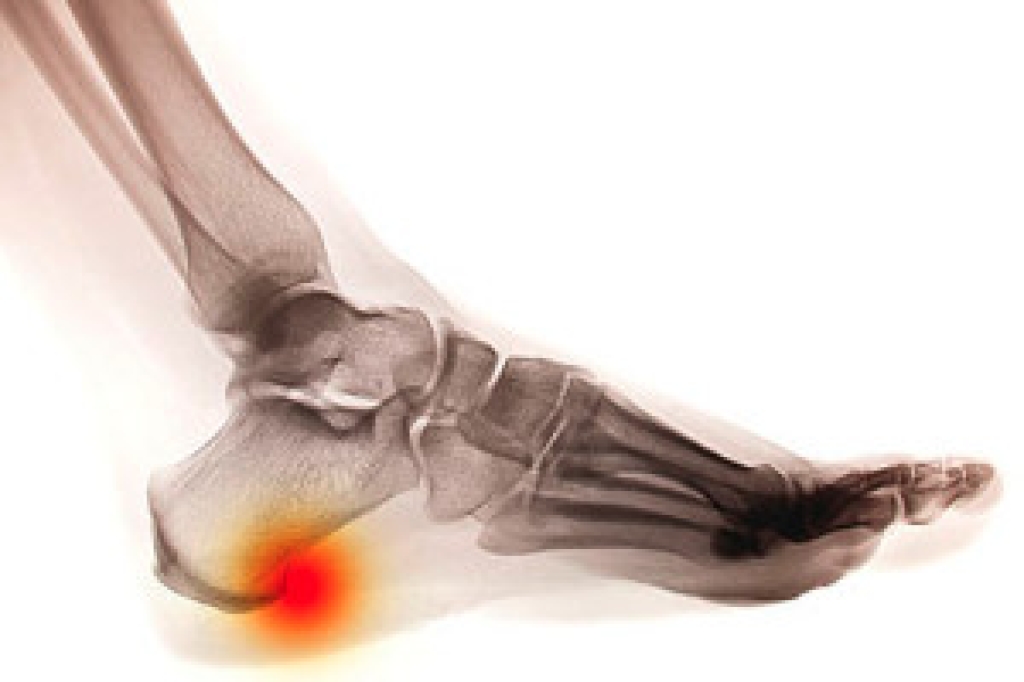

If your toe bone has broken into one or more pieces, you have experienced a broken toe. A broken toe can often be mistaken for a toe sprain, however during this type of injury, you may actually hear the bone break. If left untreated, a broken toe can alter your walking or running, and leave you in a great deal of pain. Common symptoms that often accompany a broken toe may include throbbing pain, swelling, bruising or discoloration of the surrounding skin, dislocation of the toe, and difficulty bearing weight on the affected toe. Stubbing the toe, or having an object dropped on it, are the most common causes of a broken toe. To treat a broken toe, a podiatrist may recommend a splint to help support the toe, or surgery for more severe cases. In order to distinguish a toe break from a sprain, it’s suggested you consult with a podiatrist for professional care and a proper diagnosis.

Although most people try to avoid foot trauma such as banging, stubbing, or dropping heavy objects on their feet, the unfortunate fact is that it is a common occurrence. Given the fact that toes are positioned in front of the feet, they typically sustain the brunt of such trauma. When trauma occurs to a toe, the result can be a painful break (fracture).

Severe toe fractures may be treated with a splint, cast, and in some cases, minor surgery. Due to its position and the pressure it endures with daily activity, future complications can occur if the big toe is not properly treated.